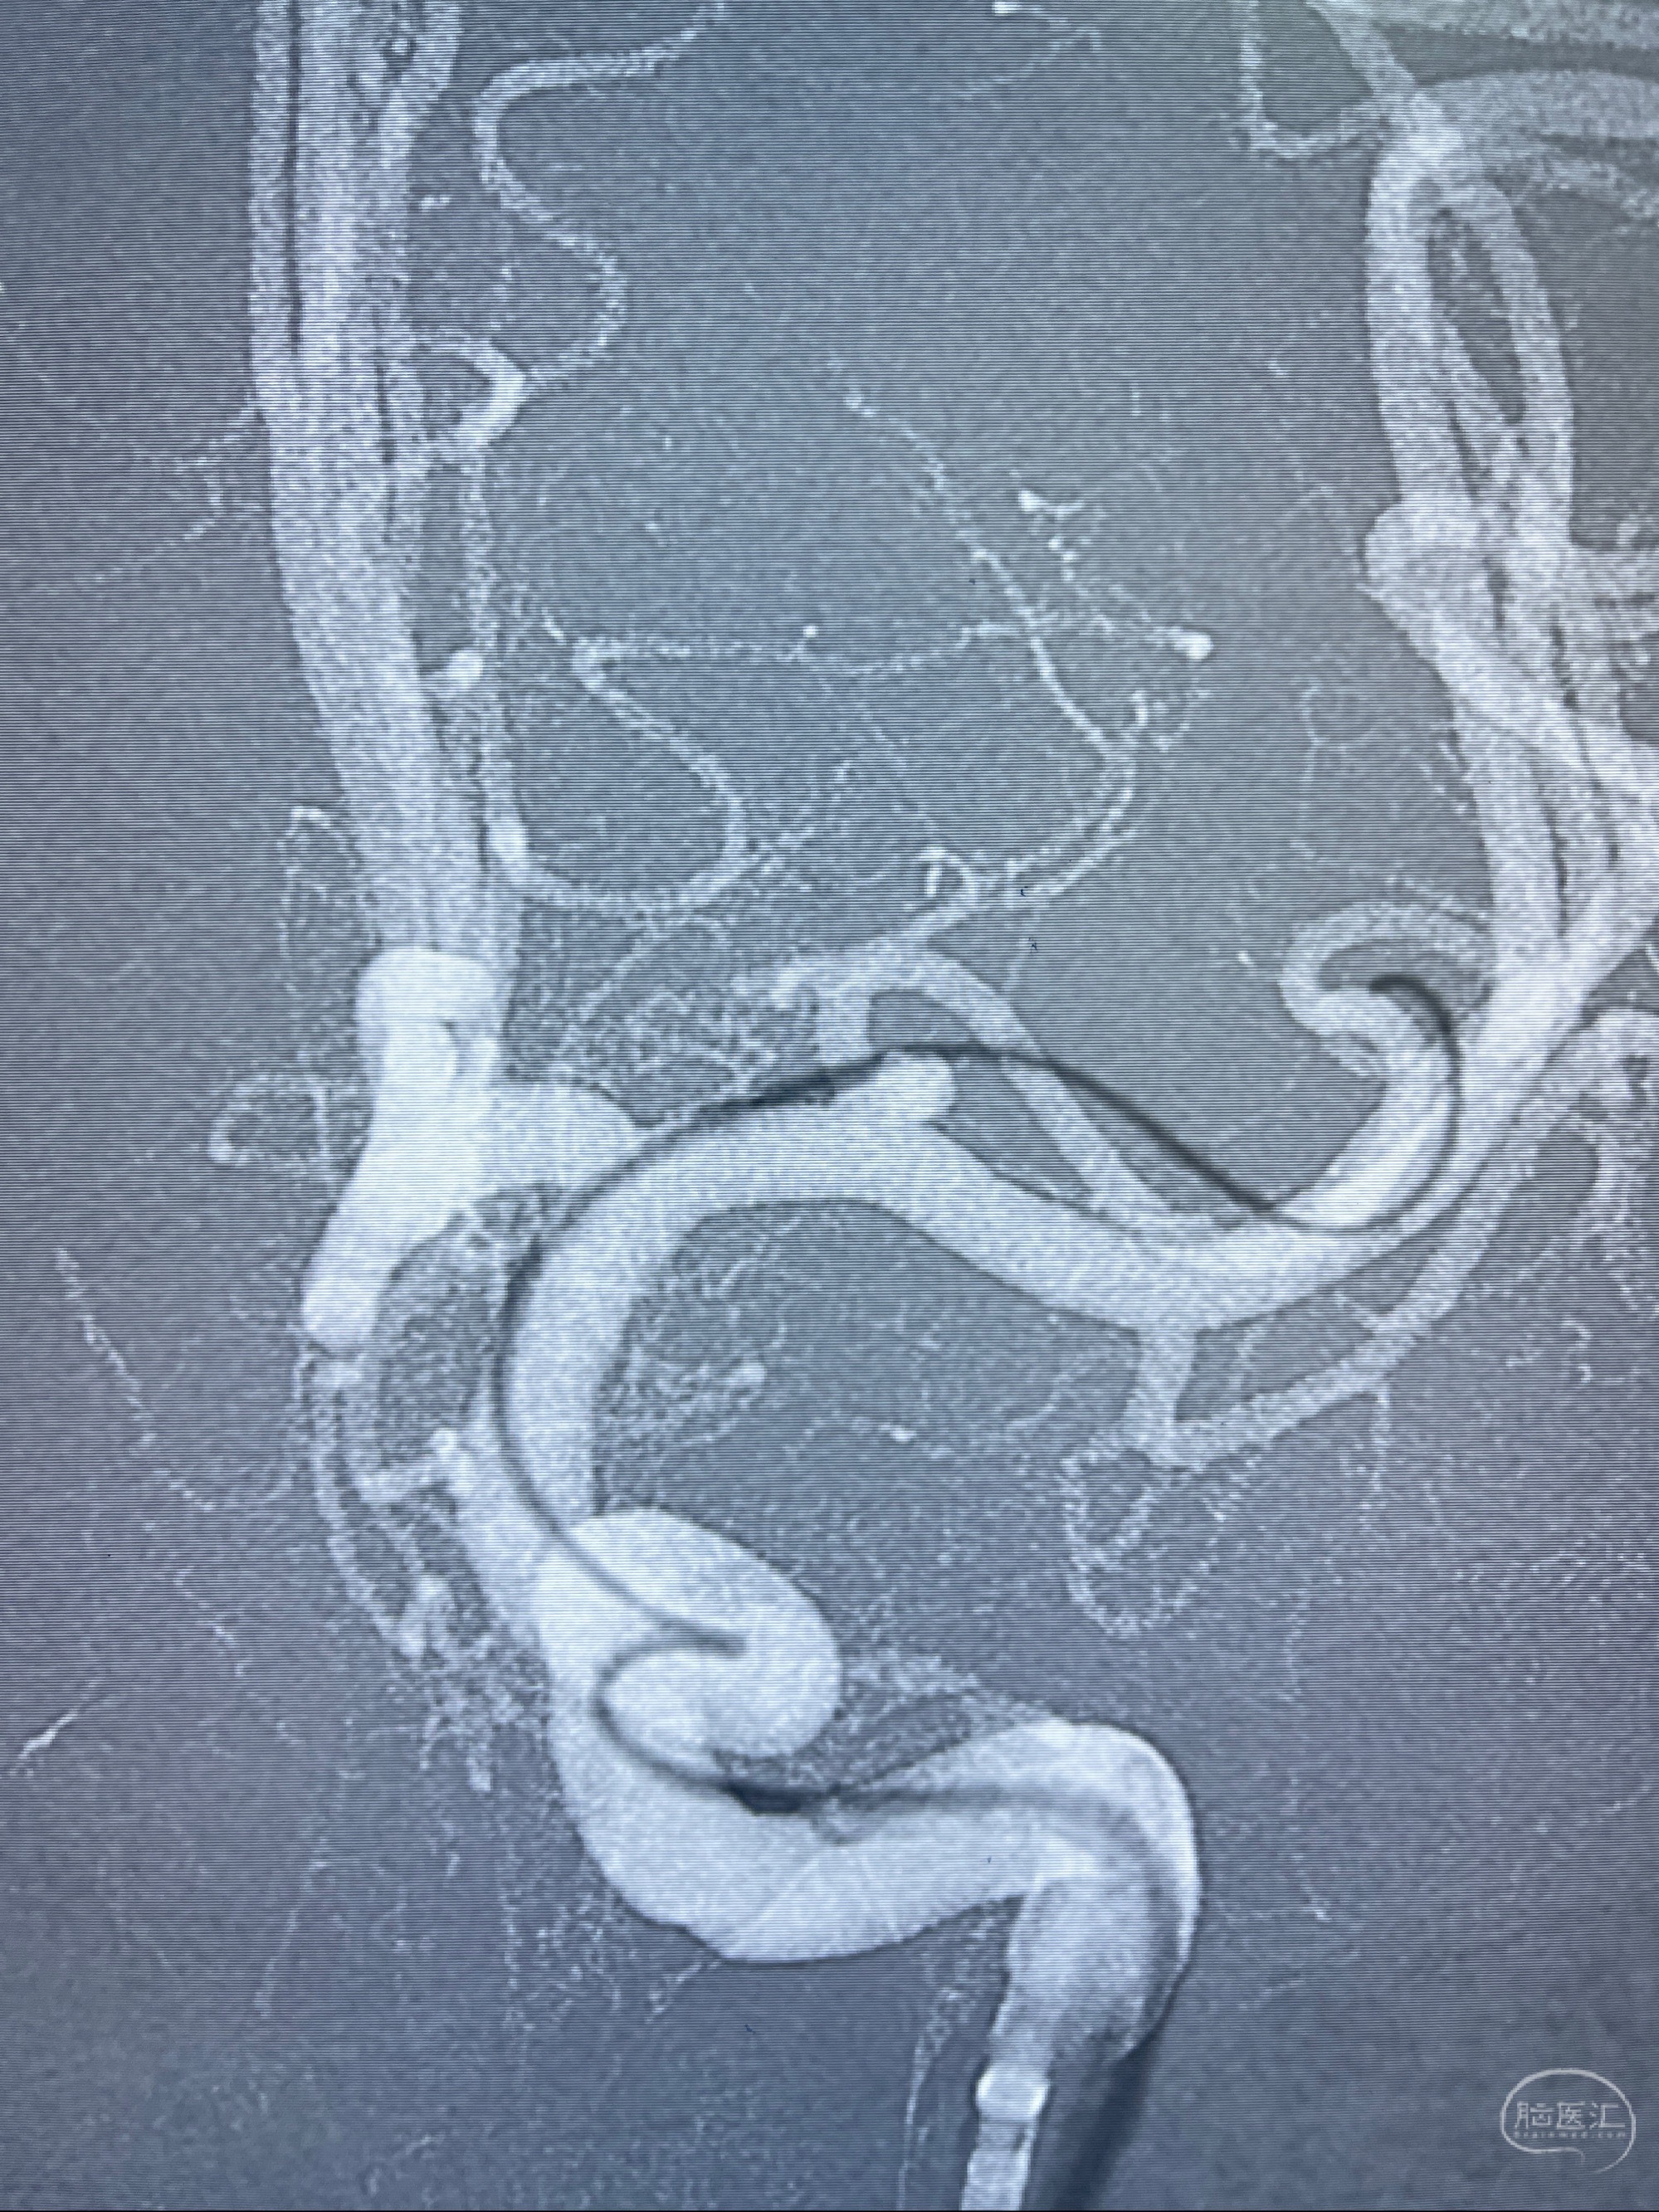

麻醉苏醒佳,遵嘱动作

术后即刻CT